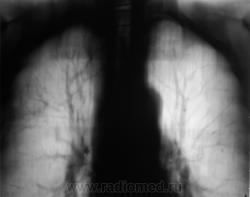

Произведена рентгенограмма в прямой стандартной проекции и томограммы в стандартных срезах.

«Пневмония», сразу показалась какой-то «фердиперсовой», с учетом лечения в стационаре ранее, довольно хорошего самочувствия пациента и наличием весьма «убогой» клиники. После проведения исследования было рекомендовано провести противовоспалительное лечение, исследование мокроты с целью проведения дифференциальной диагностики, рекомендована консультация фтизиатра.

Мы в протоколе, конечно, отметили, о возможности инфильтративного туберкулёза, д/д ряд даже не дали.

Коллега фтизиатр кричит, что «это не мое», говорит об определенной динамике по рентгенограммам и томограммам, опирается на наличие воздуха в бронхах (воздушная бронхограмма), гнет линию в сторону пневмонии. Да, его коллегу, тоже можно понять, ибо, давно «план» по выявлению выполнили и даже перевыполнили, его тоже, по всей видимости, за выход за «рамки плана» по голове -то не погладят.

Но, мы стойко несмотря ни на что, стояли на тубере.

Пациент 4 месяца, по полной программе отлежал в областной конторе, ЦВК утвердило «инфильтративный». После выписки был направлен под надзор фтизиатра по месту жительства. Ниже иллюстрации после выписки.

Снимки сегодня.